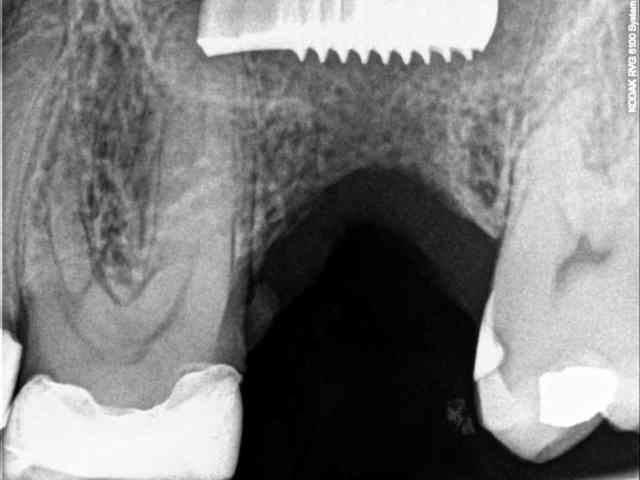

ce matin après avoir reçu un coup de téléphone d'une consœur, j'ai reçu en urgence un patient avec un petit souci...

l'implant a été posé en aout, apparemment dans une zone SA3 et apparemment sans utiliser la technique de Summers (d’après le patient , pas de biomat utilisé). je dis apparemment, car on se doit de tout mettre au conditionnel avec les patients.

ce dernier a perdu la vis de cica peu de temps après la pose et a mis plusieurs semaines pour se la faire remettre.

bref, depuis 4 jours il a mal, il consulte et là, c'est le drame...

migration dans le sinus et début d'infection.

je ne suis pas sure toutefois d'être en face d'une CBS dans la mesure où ma le teste de Walsava est négatif, et où l'implant semble accolé au plancher sinusien.

j'espère qu'il est simplement sous la membrane de Schneider, auquel cas il devrait mettre assez facile d'aller le chercher.